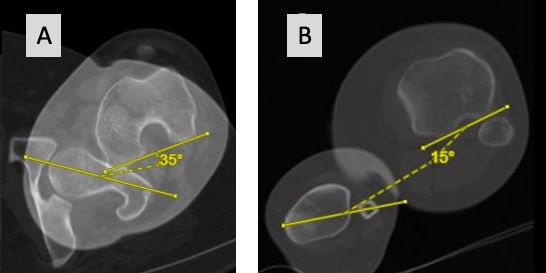

Without knowing all the details of this complex 3-D biomechanics of the patellofemoral joint, Insall has recommended to realign the prosthesis to the extensor mechanism during TKA surgery already 40 years ago. He introduced the tibia tubercle axis (TTA) for rotational alignment (Fig 21) which brings the TT under the trochlea from extension until deep flexion in all cases [1]. Most surgeons follow this simple technique but never thought about the wide variation of the TT to the proximal tibia anatomy. During the last decade several studies using 3-D imaging have shown that proximal tibia axial deformity is common in TKA patients and the TT position to the proximal tibia anatomy is very variable [22,30,48]--. Furthermore, it could be demonstrated that in varus knees external torsional deformities showed a clear correlation to the severity of the frontal malalignment [52]. The most commonly used measurement technique for knees with TKA is the anterior tibia tubercle angle (ATTA), which measures the angle between two lines (Fig 1 B and C) [4,30].

On average this angle is 25° with a wide range from 4 to 50°. 49% of knees show outliers > 5° and 15% more than 10°. Roughly 5° is equal to 1 mm, which correlates to the 5 mm of the TT-TG distance. Axial tibia component IR malalignment of more than 5° to the TT is clinically relevant [3].